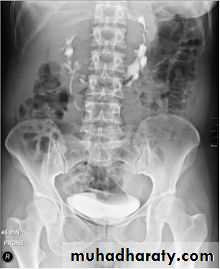

IVU

Large kidney .

Lobulated out-line.

Distortion of pelvi- calyceal system depend on cyst size, number and position.

In advanced cases there is elongation and stretching of minor and major calyces ( spider leg).

In advanced cases IVU shows non-functioning kidney .